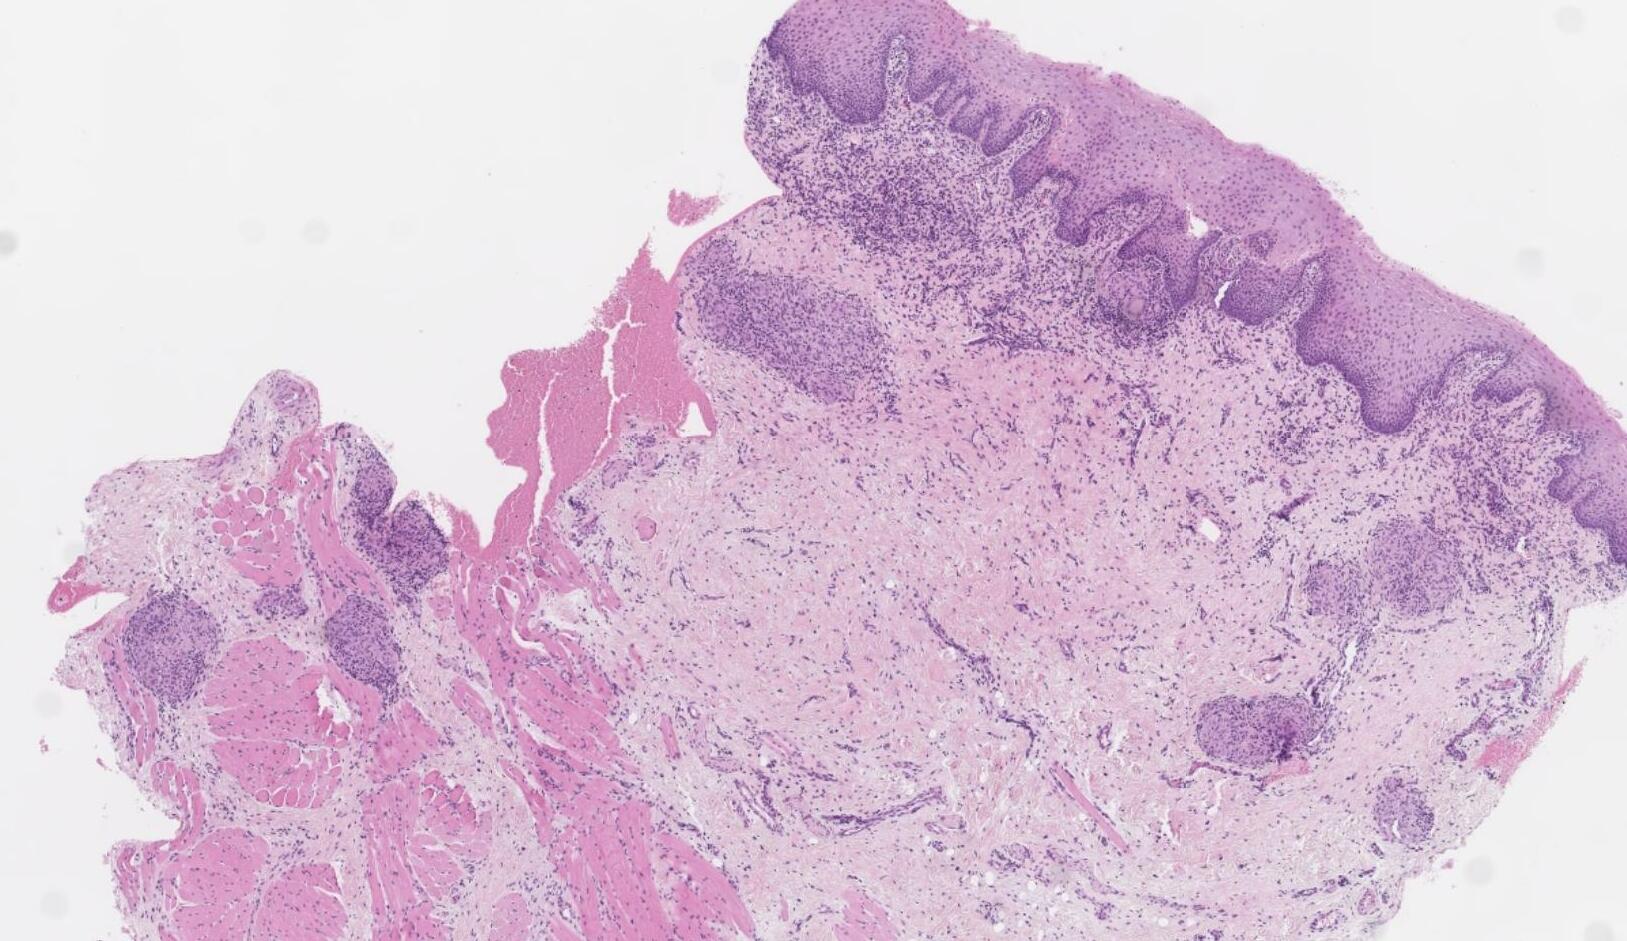

• Nodular mucosa with circumscribed tumour with infiltrative periphery • Large cells with eosinophilic granular cytoplasm • Is surface epithelium normal?

Case 4- Salient points

??

Case 4 Diagnosis

Granular cell tumour